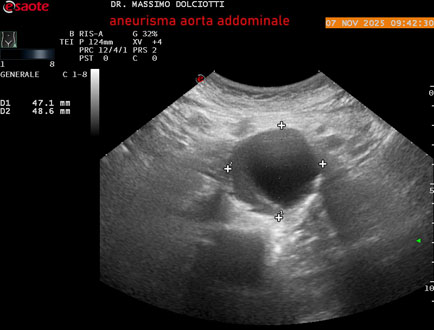

Data inserimento: 11/11/2025

Ecografia del: 07/11/2025

Strumento: Esaote MyLab Eight

Sonda: Convex Multifrequenza 1-8 MHz

Età Paziente: M 60 anni

Motivazione dell'esame: follow up per aneurisma dell'aorta addominale.

Commento all'esame: le immagini ed il video documentano la presenza dell'aneurisma dell'aorta addominale sotto-renale, con diametro antero-posteriore massimo documentato di 47 / 48 mm.

Conclusioni: aneurisma dell'aorta addominale in follow up (abdominal aortic aneurysm follow-up).

Presentazione: Dr. Massimo Dolciotti - Ancona

Elaborazione digitale: Andrea Dini - Ancona